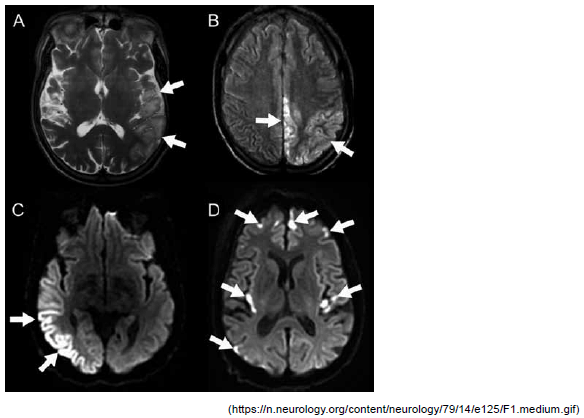

A imagem a seguir refere-se a um paciente masculino, 30 anos, com antecedentes de crises convulsivas, perda auditiva progressiva e diabetes mellitus tipo 1 e admitido com quadro sugestivo de ataque isquêmico transitório. Com base nesse exame, o exame complementar ideal para a confirmação da suspeita diagnóstica desse paciente, a ser coletado na emergência, é:

Paciente feminina, 32 anos, em sua segunda gestação com aumento dos níveis pressóricos no terceiro trimestre e no trabalho de parto, após 5 dias de puerpério foi admitida no hospital com quadro de diminuição de acuidade visual à esquerda, crise convulsiva tônico-clônica generalizada e sonolência. Realizada a ressonância de crânio a seguir.

Assinale a alternativa correta referente ao diagnóstico mais provável dessa paciente.